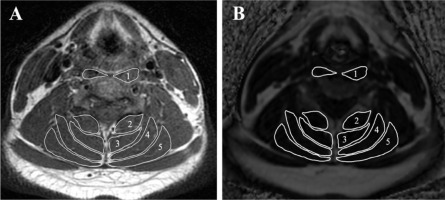

First, a T1-weighted sequence was used to enhance the fatty tissue signal and suppress the water signal. Using the Miele-lxiv image processing software (available at: https://miele-lxiv.macupdate.com/), regions within the facial borders of the longus colli and capitis (LCo & LCa), multifidus (MF), semispinalis cervicis (SSCe), semispinalis capitis (SSCa), and splenius cervicis and capitis (SpCe & SpCa) were manually drawn (Figure 1). After mapping the specific muscles in the T1-weighted sequence, the fat fraction image was used to quantify FI in each muscle. The software calculates the average signal intensity for fat accumulation in each area of interest. The mean of the bilateral muscles at C2/3, C4/5, and C6/7 was used to define the total FI.

Figure 1

Evaluation of muscle fat infiltration at C4/5. (A) T1-weighting image, (B) fat fraction image using the threshold technique with the Miele lxiv. The following measured muscles were included: 1 – longus colli and capitis, 2 – multifidus, 3 – semispinalis cervicis,4 – semispinalis capitis, and 5 – splenius cervicis and capitis